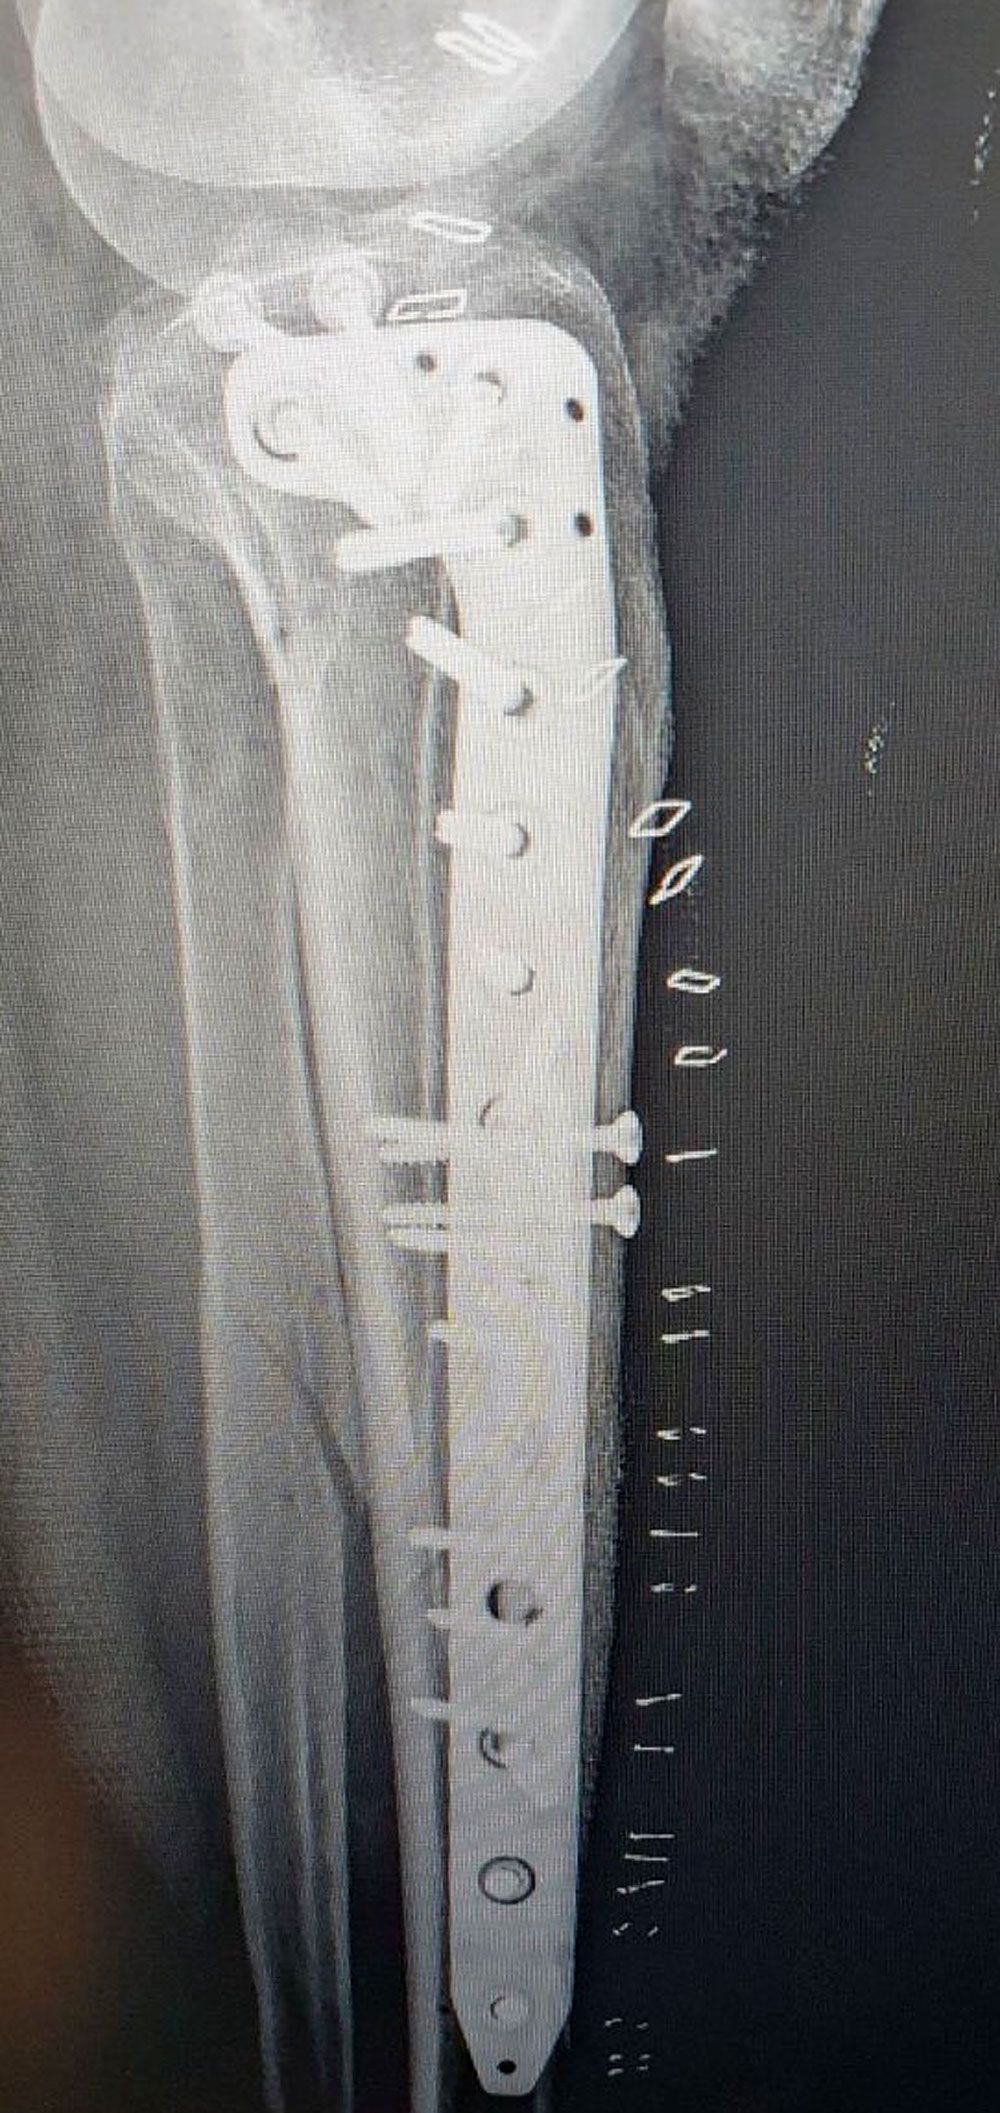

Σοβαρό ενδαρθρικό κάταγμα κνημιαίου πλατώ (Schatzker VI) — υψηλών απαιτήσεων αποκατάσταση με στόχο ανατομική ανάταξη και λειτουργικότητα γόνατος.

Αντιμετωπίσαμε ένα από τα πιο απαιτητικά και σύνθετα τραύματα στην ορθοπαιδική: σοβαρό ενδαρθρικό κάταγμα κνημιαίου πλατώ, Schatzker VI.

Μια επέμβαση υψηλών απαιτήσεων, που απαιτεί ακρίβεια, στρατηγική και απόλυτη προσήλωση στη λεπτομέρεια, με στόχο την ανατομική αποκατάσταση της αρθρικής επιφάνειας και τη διατήρηση της λειτουργικότητας του γόνατος.

Το αποτέλεσμα μας ικανοποιεί.

Gold standard: ORIF (Open Reduction and Internal Fixation)

- Διπλή πλάκα (medial + lateral plating)

- Dual plating (medial + lateral plating)